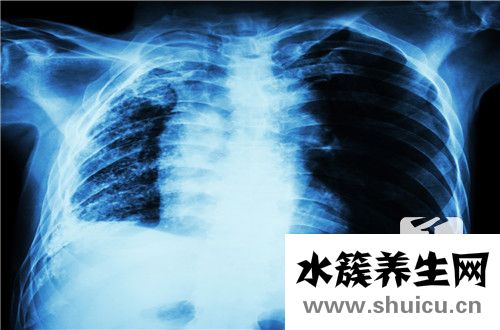

肺鈣化的最常見原因是肺部炎癥。 常見疾病是肺結核,其次是肺炎。 氣管炎也是由肺癌和其他疾病引起的,尤其是由結核病引起的肺鈣化。 由于這種疾病會導致感染,因此如果痰中有血液,胸痛和其他癥狀,應進...